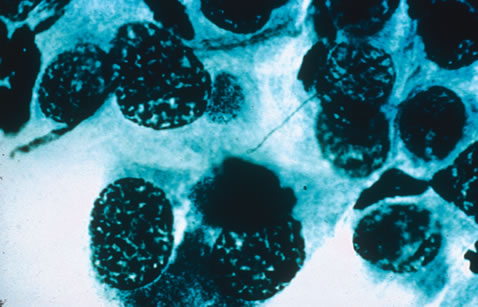

HIV was previously known as human, T-cell lymphotropic virus type 3 (HTLV-III) and lymphadenopathy-associated virus (LAV). There are two known types of virus: HIV type 1, which causes AIDS, and HIV type 2, the disease spectrum of which is uncertain. HIV type 2 has been found in some African cases of AIDS. HIV is a retrovirus, meaning it contains a reverse transcriptase enzyme that produces a double-stranded DNA copy (cDNA) from the virus RNA genome (Fig. 9).24 HIV infection involves attachment of viral envelope glycoprotein to the CD4 molecule present on T-helper (T4, OKT4, or CD4+) cell surfaces. The virus then fuses with the cell membrane, enters cytoplasm, loses its envelope, and reverse transcription of RNA to DNA occurs. Viral DNA becomes integrated into host cell DNA as latent provirus, in which state it may go unrecognized by the immune system. The proviral DNA can then be transcribed and translated, producing viral proteins and viral genome RNA, which assemble and bud through the host cell plasma membrane as new virions. Antigenic stimulation of lymphocyte activity appears to be important in conversion from latency to progressive infection.

Fig. 9. An electron micrograph of the human immunodeficiency virus type 1 (HIV-1) in the retina.